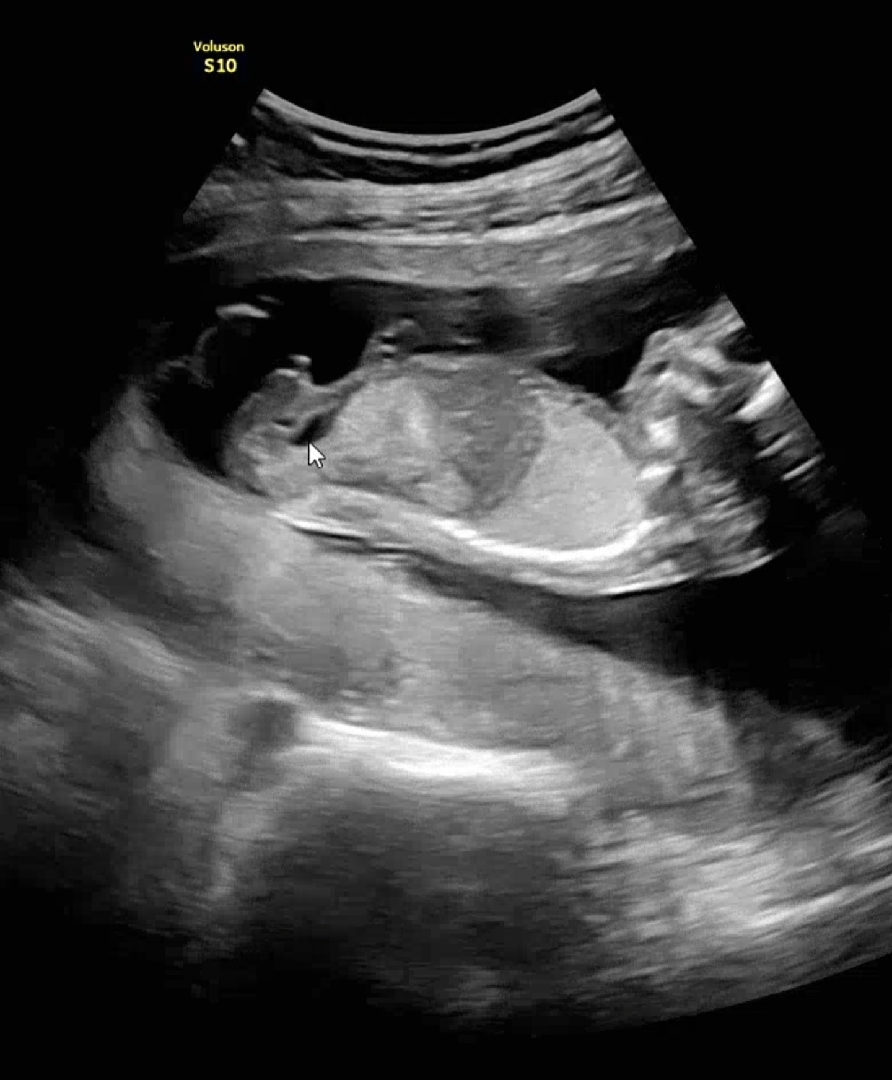

16주 1일 초음파입니당! 병원에서 초음파하고 성별이 뭔지 여쭤봤는데, 초음파 보시면서 여기 튀어나와있네요~ 한마디 하셨는데 그게 말씀 해주신거라고 하시네요 😂 아들이라는 뜻 같은데 명확하게 말씀을 안해주셔서 확실하게 알고싶어서 올립니다! 잘보시는 분들 도와주세요~ 궁댕이쪽에선 안찍어주셔서 옆모습 밖에 없어요 ㅜㅜ

사진 하나 더 추가합니다 !! 마우스 커서 있는 쪽이 🌶라고 보신거같아요 🥹